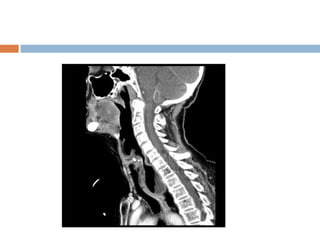

Images obtained during barium swallow videofluoroscopy

demonstrating an intermediate-sized Zenker diverticulum

 Contrast video-fluoroscopy:

 Constant monitoring of the swallowing

(single shot barium swallow may miss small

pouch)

 Able to see pouch from different angles

 Size, location, and character of the mucosal

lining

 Function of the pharyngeal muscles

 Presence or absence of gastric reflux

 Contrast study should include lower oesophagus

& stomach – lower oesophageal carcinoma &

hiatal hernia can coexist with pharyngeal pouch